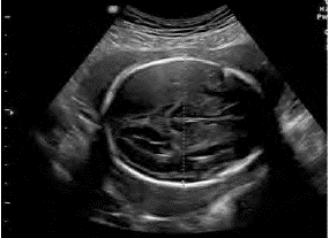

1.38.4四、中晚期妊娠

1.38.12十二、胎儿畸形